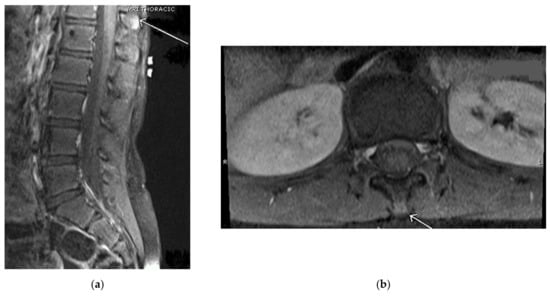

Our second case involves an active, healthy 18-year-old female cheerleader and gymnast who was diagnosed with Baastrup’s disease in 2016 at the age of 12. She initially presented to the clinic in 2016 complaining of one year duration of low back pain that started after doing tumbling exercises in gymnastics. Her back pain did not improve after multiple periods of rest. She had roentgenograms (X-rays) that were negative; however, her lumbar MRI showed a minor L5-S1 disc bulge without focal disc herniation. Her single-photon emission computed tomography (SPECT) focused on the lumbar spine showed abnormal uptake in bilateral sacroiliac joints with no other abnormalities in the spine. The patient saw a rheumatologist who did not feel she had an inflammatory spondyloarthropathy. Based on the patient’s clinical presentation of pain only on extension, a working diagnosis of Baastrup disease was suspected. In 2016, the patient underwent an injection of a solution containing 1 ml of 0.2% ropivacaine with 40 mg Kenalog into the interspinous ligament between L2 and L3 in hopes of alleviating her chronic back pain. Upon follow-up from the procedure, one month later, the patient no longer experienced pain with back extension but was referred to physical therapy for ongoing management. After completing her treatment course, she resumed cheerleading without restrictions. However, she returned to the pain clinic in 2017 while complaining of the same back pain. She noted the pain started after repeated backbends. Her X-ray showed no abnormalities. Conversely, her lumbar MRI in 2017, revealed a small focal area of soft tissue edema along the L3 spinous process into the L2-L3 interspinous ligament, which is compatible with the earliest findings of Baastrup’s disease (see Figure 2).

Figure 2. (a) Magnetic resonance imaging (MRI) lumbar spine sagittal view shows an arrow pointing to a small focal area of soft tissue edema along the L3 spinous process into the L2-3 interspinous ligament without underlying bone marrow edema, compatible with the earliest findings of "kissing spine" Baastrup’s disease. (b) MRI lumbar spine coronal view shows an arrow pointing to a small focal area of soft tissue edema along the L3 spinous process.